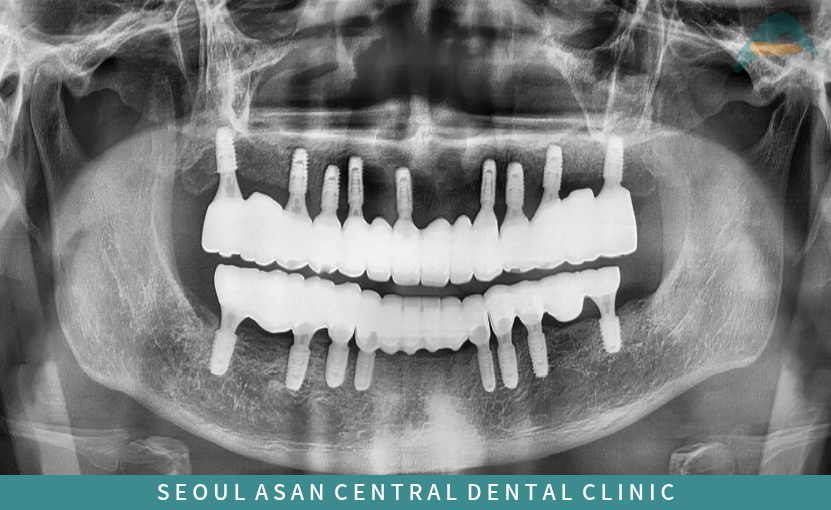

전체 임플란트 전

구강 관리 불량과

심한 치주염으로 인해

다량의 치석이 침착되어 있는 경우

전반적으로 동요도가 심하며,

다수 어금니의 상실로

교합 고경이 무너진 상태로

아래 치아들이

위로 솟구쳐 올라와 있는 경우에는

안타깝지만 발치가 불가피한데요.

단대오거리치과 파노라마 사진에서도

치아를 단단하게 잡고 있어야 할

치주조직들이 심한 염증으로 인해

많이 약해져 있는 것을

확인할 수 있었습니다.

이런 경우에는 정밀한 검사와 진단을 통해

전체 치아 발치 후 전체 임플란트를 통해

치아의 기능과 심미성 회복이 필요합니다.